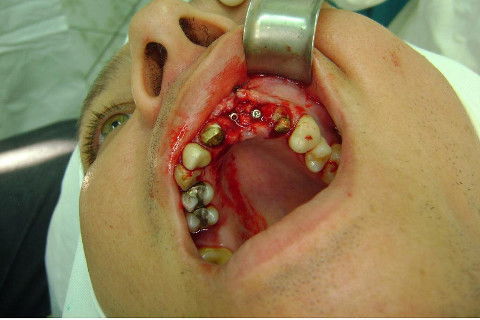

Cirurgia realizada hoje de manhã...No planejamento percebi medindo espessura do rebordo com especímetro que as medidas não estavam muito boas, ou o ideal, em torno de 4,5 a 5 mm ate´o terço médio do rebordo e melhorava no final, com 6 a 7 mm. Optei então por uma pequena expansão usando os expansores rosqueáveis. Aconteceu uma pequena fenestração na hora da fixação dos implantes, especialmente na região do 22 que fraturou o início da tábua óssea, mas não me preocupei porque não foi mais do que 2 mm de fratura em direção apical, o implante ficou infraósseo e com boa estabilidade (60 N no 21 e 40 N no 22). Esta fratura tb não deixou osso completamente solto, foi do tipo galho verde, deixei em posição e suturei normalmente. Só não fiz e nem estava planejado carga imediata mesmo, mais pelo motivo da oclusão inadequada do caso.